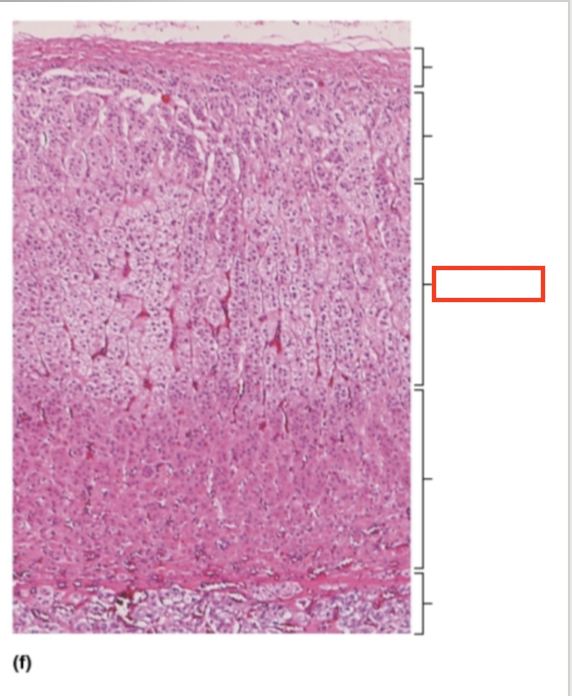

What structure is highlighted?

capsule

What structure is highlighted?

zona glomerulosa

What structure is highlighted?

zona fasciculata

What structure is highlighted?

zona reticularis

What structure is highlighted?

adrenal medulla

What tissue is shown?

adrenal gland